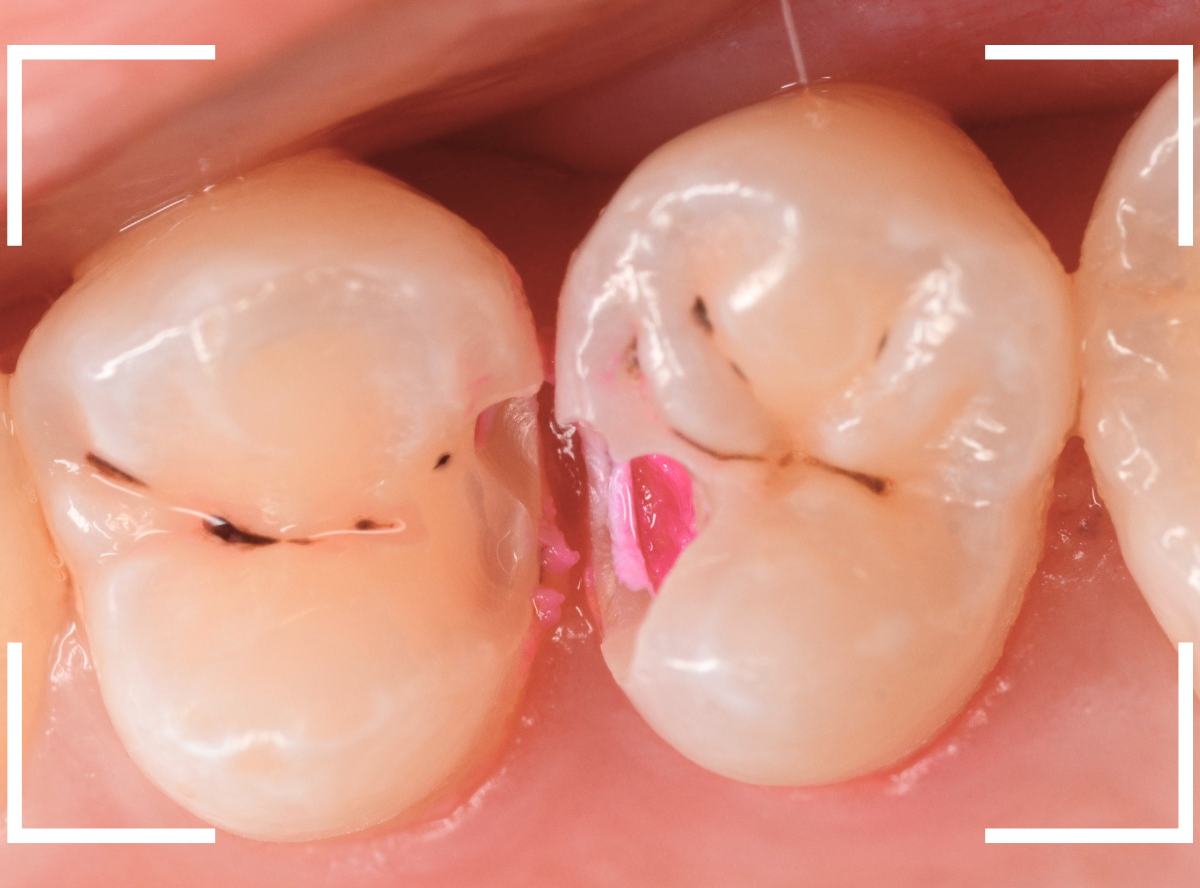

治療を開始します。

少し削ると、中からすぐに虫歯が出てきました。

ある程度、虫歯を除去したところで、う蝕検知液で確認します。

赤く染まっている部分が虫歯です。

まだまだ虫歯が中で残っている状況で、かなり深い虫歯なのが確認できます。

全ての虫歯を除去しました。

レントゲン写真からある程度確認出来ましたが、歯の神経スレスレまで虫歯が進行していました。

ここまで虫歯が進行していても、全く症状を感じない事も多いです。

そして、ある時急に痛みを感じるのです。